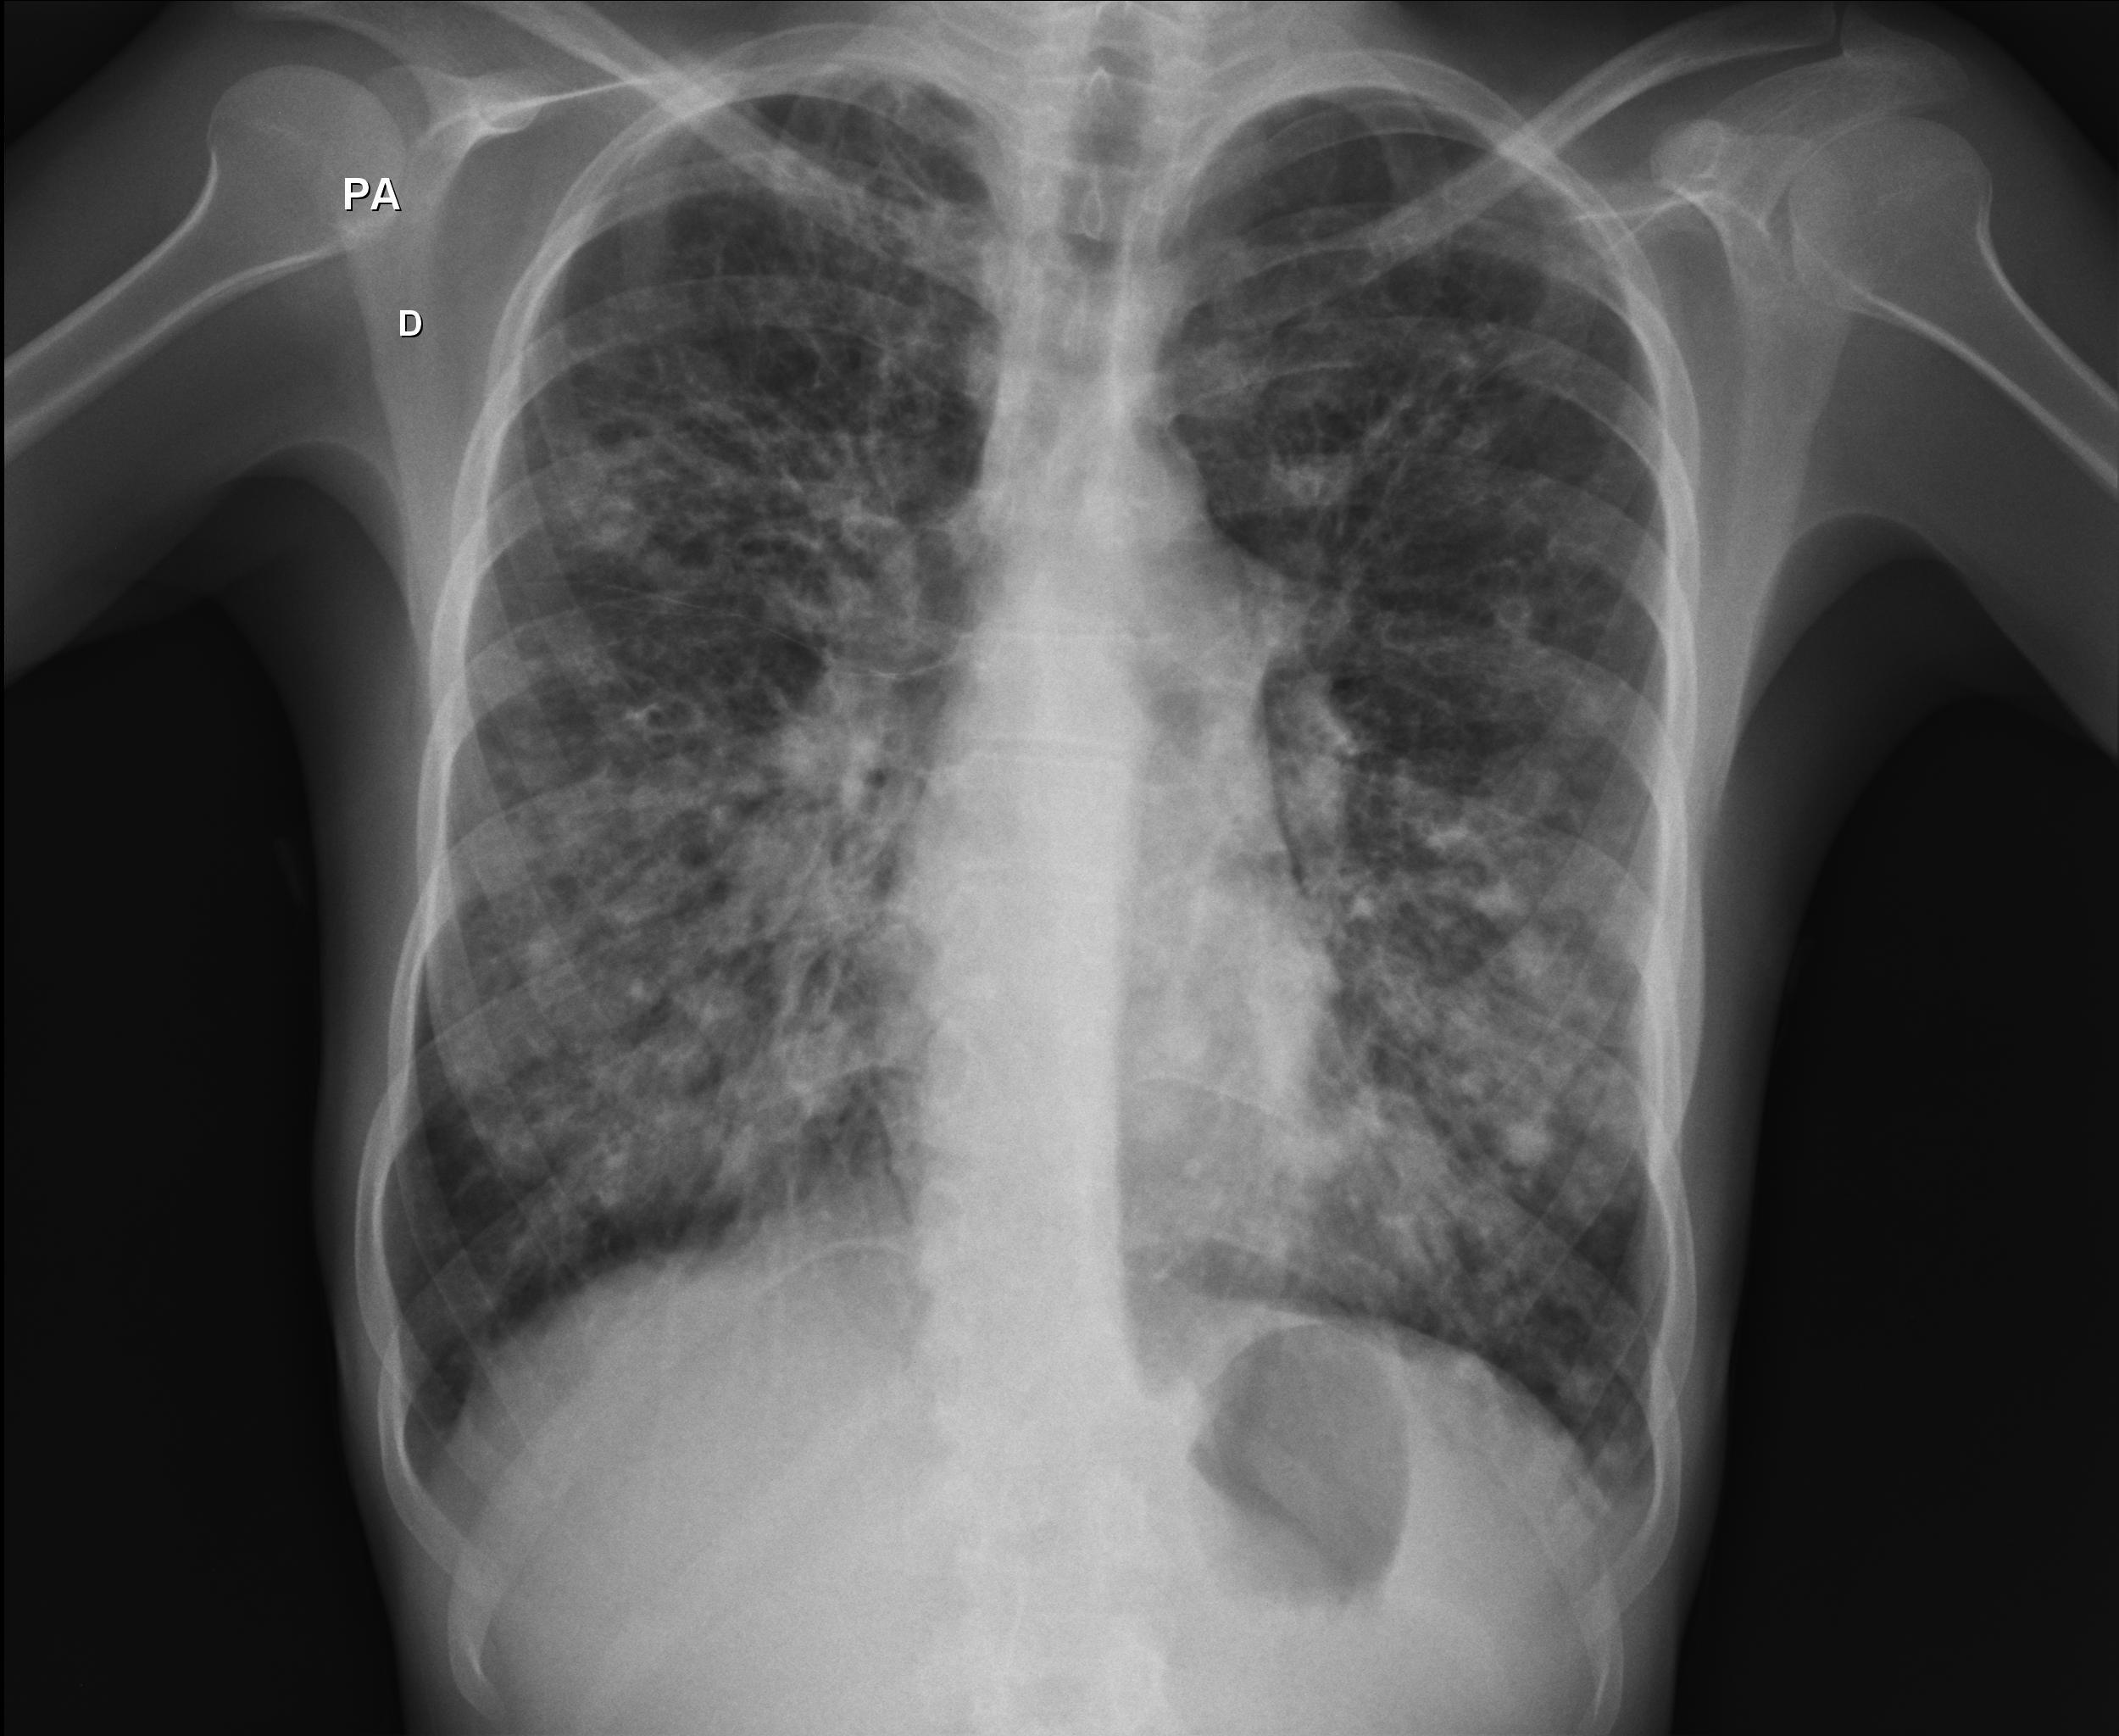

Caso relatado na Reunião de Discussão de Casos Clínicos do Hospital Universitário Prof. Polydoro Ernani de São Thiago, iniciada pelos Profs. Jorge Dias de Matos, Marisa Helena César Coral e Rosemeri Maurici da Silva, em julho de 2017. No dia 14 de junho de 2018, no auditório do HUPEST, realizou-se a apresentação e discussão do caso cujo registro é apresentado a seguir. Trata-se da discussão de onze casos em radiologia torácia, de forma interativa com a plateia, e assim ocorre também neste artigo.